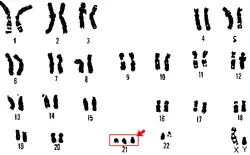

Trisomía libre

Código CIE-10: Q90.0

El síndrome de Down se produce por la aparición de un cromosoma más en el par 21 original (tres cromosomas: «trisomía» del par 21) en las células del organismo. La nomenclatura científica para ese exceso cromosómico es 47, XX,+21 o 47, XY,+21; según se trate de una mujer o de un varón, respectivamente. La mayor parte de las personas con este síndrome (95%) deben el exceso cromosómico a un error durante la segunda división meiótica (aquella por la que los gametos, óvulos o espermatozoides, pierden la mitad de sus cromosomas). Esta variante se llama «trisomía libre» o regular, y el error se debe en este caso a una disyunción incompleta del material genético de uno de los progenitores. (En la formación habitual de los gametos el par de cromosomas se separa, de modo que cada progenitor solo transmite la información de uno de los cromosomas de cada par. Cuando no se produce la disyunción se transmiten ambos cromosomas).

En aproximadamente un 15% de los casos el cromosoma extra es transmitido por el espermatozoide y en el 85 % restante por el óvulo.[24]